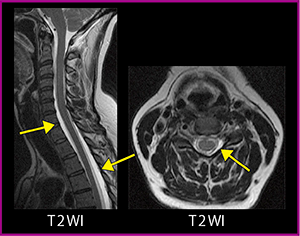

●低髄圧症候群

低髄圧症候群は,まれな疾患のため診断がつきにくい。脳では造影検査で硬膜が厚くなり,増強効果を示す所見となるためわかりやすいが,脊髄では脳脊髄液の漏出の有無,部位を確認する必要がある。脊髄硬膜外に脳脊髄液が漏出していると,通常は見えない硬膜を確認でき,硬膜外腔にT2強調画像で高信号(液体)が認められる(図6)。造影T1強調画像でも,造影剤の分布から漏出箇所を確認することができる。

Vargasら9)は,自発性頭蓋内圧低下症の治療前のT2強調画像で,硬膜外の静脈が拡張する所見があると報告している。硬膜外には非常に多くの静脈があり,MRIではこれらの静脈もよく観察することが重要である。

図6 低髄圧症候群(40歳代,女性)